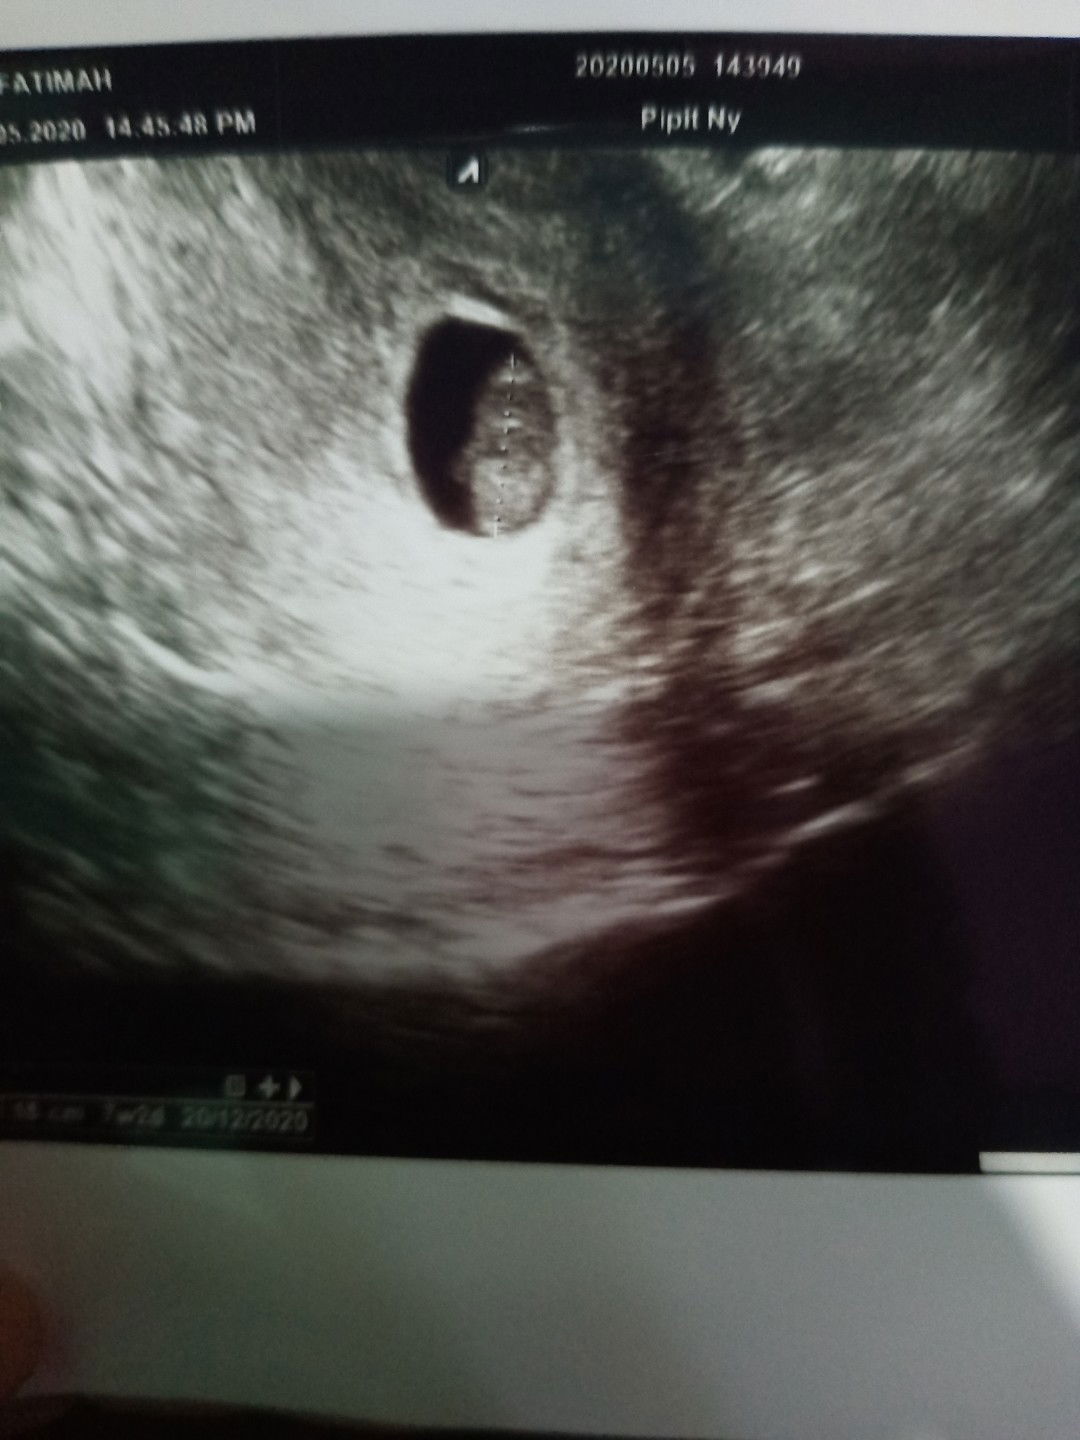

Moms, saya sedang hamil 29w3d. Kemarin kontrol rutin dan kata dokternya ari ari si baby masih dibawah & nutupin jalan lahir. Dokter si bilang masih bisa geser ari arinya. Tp kalo evaluasi bulan depan gak geser juga, gk boleh maksain lahiran normal. Sebenernya mau normal atau SC sama aja perjuangannya. Moms ada juga gak yang punya pengalaman ari ari dibawah/plasenta previa diusia TM3. Sharing dong moms #bantusharing